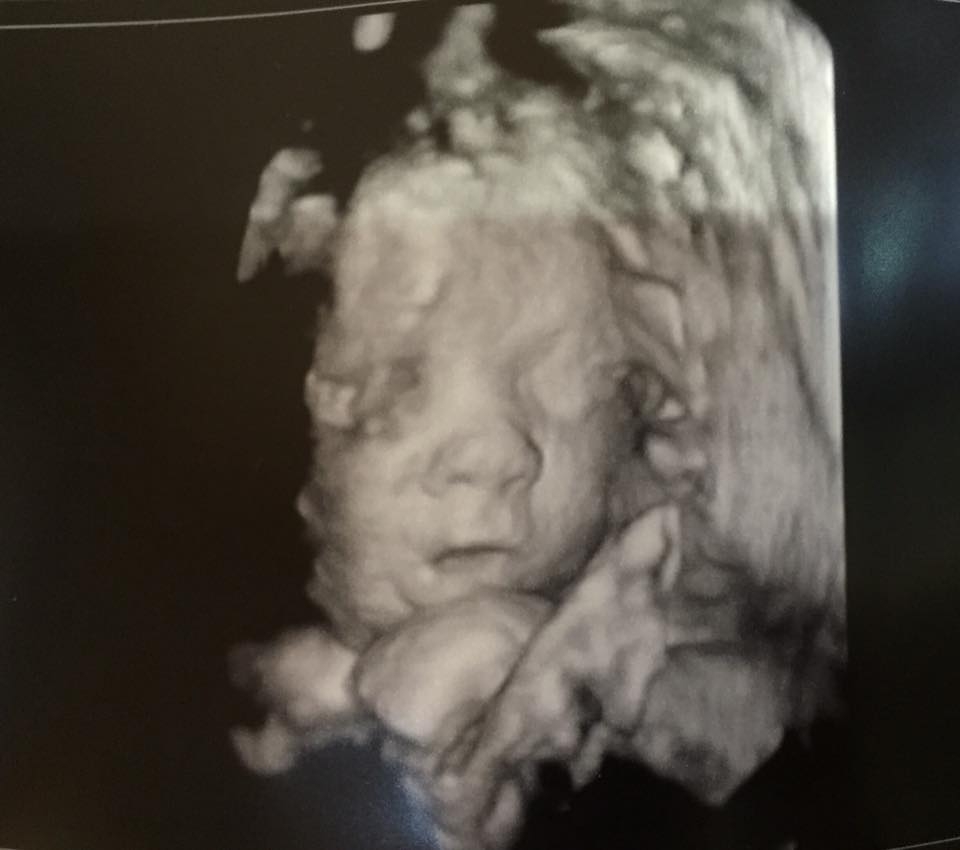

So I had my ultrasound today.....and the placenta is at 4cm!!! Three weeks ago it was at 1.1cm and the doctor wanted it to be at least 2cm in order to allow me to attempt a vaginal birth. Well little guy had a growth spurt and it moved way beyond what the minimum criteria is! Yay! This was the first time my mom came to an ultrasound so it was even more of a special day for us. We got to see the baby open and close his eyes too. Little guy is still measuring right on track and is weighing 3lbs 9oz. I hope you don't mind me sharing a pic here vs. the other thread. I am just so in love with him!